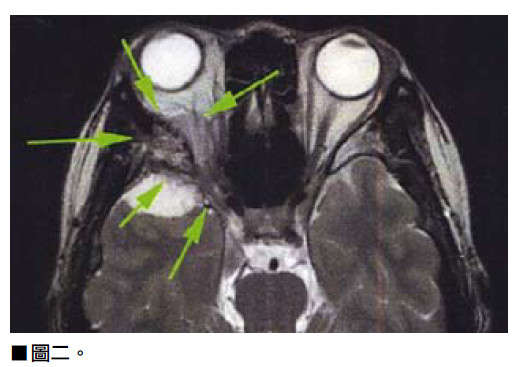

K小姐今年4月來求診,她的右眼持續6個月視力模糊並夾雜乾澀的感覺,同時眼睛有紅筋,還經常覺得眼睛疲倦。K小姐先後見過兩位眼科醫生做過眼部檢查,眼底及眼內都沒有發現任何異狀,醫生推斷可能與她工作壓力大有關,給予眼藥水滴眼睛,但視覺模糊的程度似乎日漸嚴重。最近她發現手腕及下手臂位置,從1月起出現一些皮膚泛紅的現象,泛紅部位是在皮膚表層,她不會覺得痛或灼熱,通常情況只出現3至4天後便消失,驗了血都沒有任何發現。就在她一籌莫展的時候朋友介紹她到筆者診所,朋友說如果頸椎壓到神經線,也可能影響視力或造成眼乾。筆者幫K小姐做了肌肉測試、神經反射測試以及頸椎活動檢查,雖然患者有一些頸部問題,但感覺她眼睛的症狀與頸椎沒有太大關係,可能是視覺神經線的問題。判斷後便立刻幫她做了腦部及頸椎的磁力共振掃描。果然發現她腦內有一個良性腫瘤壓着右邊視覺神經線,(見圖一、圖二、圖三)而這就是她半年來視力模糊的原因。後轉介給腦神經外科醫生進行腦部手術移徐腫瘤,手術後K小姐逐漸回復視力。

K小姐的情況是腦部良性腫瘤壓着右邊視覺 神經線引發視線模糊,筆者也談一談因為頸 椎壓到神經線影響視力或造成眼乾,該如何 治療。如果檢查後發現患者頸椎錯位時,脊 醫會為患者矯正錯位,經過矯正後患者視覺 能力通常都能夠改善。但前提當然要先確定 患者的病理,才能訂立治療方案。 讀者可能好奇,為甚麼姜小姐眼睛感到不適 卻會向脊醫求診。筆者想在此解釋脊醫也是 一線醫療人員,很多人以為脊醫是輔助醫 療,又或者認為脊醫是做物理治療!其實脊 醫的專業醫學教育及訓練,已足夠令我們具 備專業的學術資格來找出患者的病理問題。 脊醫能為患者作出診斷、治療,及在需要時 轉介患者至其他專科西醫 。